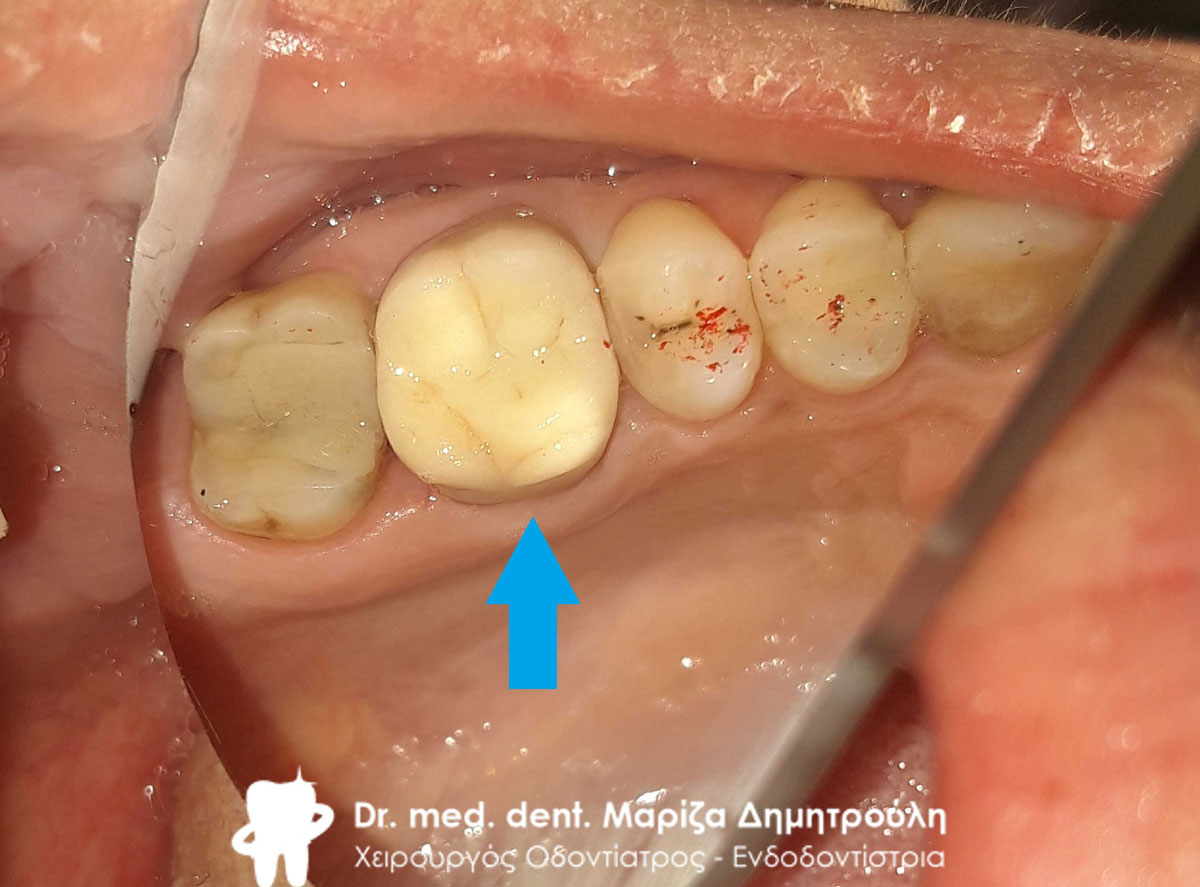

Τελική εικόνα όλων των δοντιών πριν τη λήψη αποτυπωμάτων

Τελική εικόνα όλων των δοντιών πριν τη λήψη αποτυπωμάτων

Τελική εικόνα της ολοκεραμικής γέφυρας ζιρκονίου στην κάτω γνάθο

Τελική εικόνα της ολοκεραμικής γέφυρας ζιρκονίου στην κάτω γνάθο

Ο ασθενής ήρθε στο ιατρείο για την αποκατάσταση της αριστερής πλευράς της κάτω γνάθου. Στα δόντια έγιναν απονευρώσεις δοντιών, η ανασύσταση τους με λευκούς άξονες υαλονημάτων. Στη συνέχεια ακολούθησε ο εκτροχισμός τους, η λήψη αποτυπωμάτων και η αποστολή τους στον οδοντοτεχνίτη. Στο τέλος συγκολλήθηκε η ολοκεραμική γέφυρα ζιρκονίου στα δόντια.